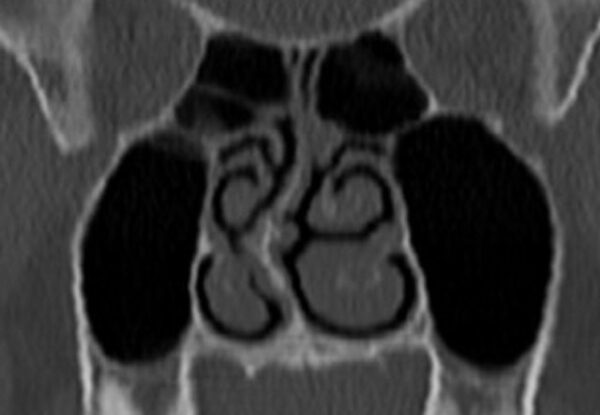

When the maxilla develops inadequately in width or forward projection, the nasal floor becomes restricted, potentially limiting airflow. This may lead to deviated septums, enlarged turbinates or adenoids and turbulent airflow. As nasal breathing becomes more difficult, mouth breathing often takes over, reinforcing dysfunctional postural and craniofacial patterns.

Deviated Septum